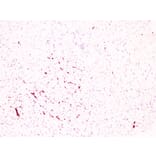

Immunohistochemistry - Anti-CD61 Antibody [ABT-CD61] (A100026)

Immunohistochemical analysis of paraffin-embedded human Spleen using Anti-CD61 Antibody.